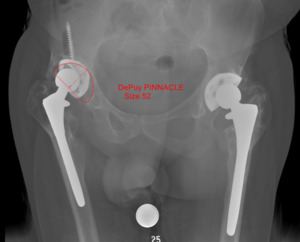

The preoperative radiograph was templated using a 52 mm Pinnacle cup (Depuy Synthes, Warsaw, IN) (Fig. 2). The patient was placed supine on the Hana table (Mizuho Osi, Union City, CA). Incision was performed from the anterior half of the iliac crest to the anterior superior iliac spine, and then extended an additional 10 centimeters towards the lateral patella. Dissection was performed down to the tensor fascia lata (TFL). The TFL was released from the anterior iliac crest, and superficial dissection continued using the TFL-sartorius interval. Rectus femoris was released from the anterior inferior iliac spine, and deep dissection was performed through the rectus femoris-gluteus medius interval. No purulence was encountered. Locating the femoral neck was difficult due to the extensive HO present. The leg was placed into extension and maximum external rotation. Capsulectomy and excision of the HO was performed down to the level of the femoral neck. The prosthesis was completely encased within heterotopic bone. The hip could not be distracted or dislocated, so additional debridement was performed around the joint to remove the HO.

The second broken cancellous dome screw was identified. The broken screw removal set could not be utilized due to the angle of the screw. Instead, an osteotome and vice grips were used to successfully remove the cancellous screw without significant bone loss. Gentle reaming proceeded up to the size 51 mm reamer. Autograft was utilized to reverse ream into the segmental and contained defect within the acetabulum. A 52 mm Pinnacle multi-hole with Gription acetabular cup (Depuy Synthes, Warsaw, IN) was impacted into 20 degrees of forward flexion and 40 degrees of abduction (Fig. 3). The acetabular cup had a primary impaction bite and was quite stable. The position of the acetabular cup was confirmed using intraoperative fluoroscopy and software that digitizes radiographs to determine positioning of the acetabular component. The acetabular cup was further secured with five 6.5mm cancellous dome screws. A 32mm head was chosen secondary to the constraints on the 10/12 femoral stem taper. A 32mm neutral AltrX polyethylene liner (Depuy Synthes, Warsaw, IN) was impacted into place. A 32mm +5mm offset PFC femoral head (Depuy Synthes, Warsaw, IN) was impacted onto the trunnion.